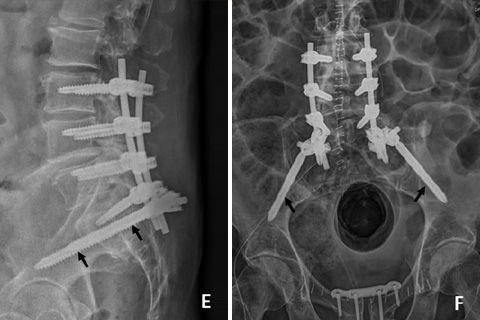

Scopri di più su ELSEVIERI risultati di un'analisi sperimentale combinata, micro-TC e micro-analisi degli elementi, dimostrano che l'ancoraggio dello strumentario per le barre di viti peduncolari nella colonna vertebrale degli anziani con scarsa qualità ossea rimane una sfida. Il nostro studio mira a valutare come l'ancoraggio osseo della vite sia influenzato dal design della vite, dalla qualità dell'osso, dalle condizioni di carico e dalle tecniche di cementazione.

L'ancoraggio dello strumentario per viti peduncolari nella colonna vertebrale degli anziani con scarsa qualità ossea rimane difficile. In questo studio sono stati utilizzati modelli di microelementi finiti per valutare l'influenza specifica del design della vite e il contributo relativo della densità ossea locale alla meccanica di fissazione. Gli impianti analizzati erano viti peduncolari Ennovate®. I risultati sono stati pubblicati sul Journal of Biomechanics nel dicembre 2017 e sono disponibili anche presso ELSEVIER.

Per saperne di più sul Journal of BiomechanicsLa strumentazione dorsale posteriore con sistemi di barre e viti peduncolari è ancora lo standard di riferimento per le procedure di fusione spinale. La vite peduncolare stessa svolge un ruolo importante in questa struttura di stabilizzazione per quanto riguarda l'ancoraggio osseo e il carico delle vertebre vicine. Tuttavia, la rottura delle viti peduncolari è riportata nell'intervallo 3-7%. [1] L'obiettivo di questo studio era quello di aumentare la resistenza meccanica di una vite peduncolare ottimizzando la sollecitazione della vite filettata per migliorare le proprietà di resistenza.

Sebbene la strumentazione con barre per viti peduncolari rappresenti ancora lo standard di riferimento per il trattamento di una vasta gamma di patologie degenerative spinali, l'ancoraggio nella colonna vertebrale degli anziani con scarsa qualità ossea rimane difficile. Tuttavia, non sono disponibili modelli per valutare l'influenza specifica dei parametri di progettazione delle viti sull'interfaccia vite-osso peduncolare. Nel nostro studio, ci siamo rivolti a sviluppare modelli di microelemento finito numerico (µFE) basati su scansioni µCT per esaminare l'interfaccia ossea della vite a livello di microscala.

Per saperne di più sul Journal of BiomechanicsLa vite Ennovate® PentaCore® è il nuovo benchmark nel mercato dei sistemi di viti peduncolari. Le viti Ennovate hanno una forza di pullout, di resistenza al taglio e una resistenza complessiva significativamente più elevate rispetto alle altre viti attualmente disponibili sul mercato, conclude uno studio pubblicato di recente sul Journal of Biomechanics.